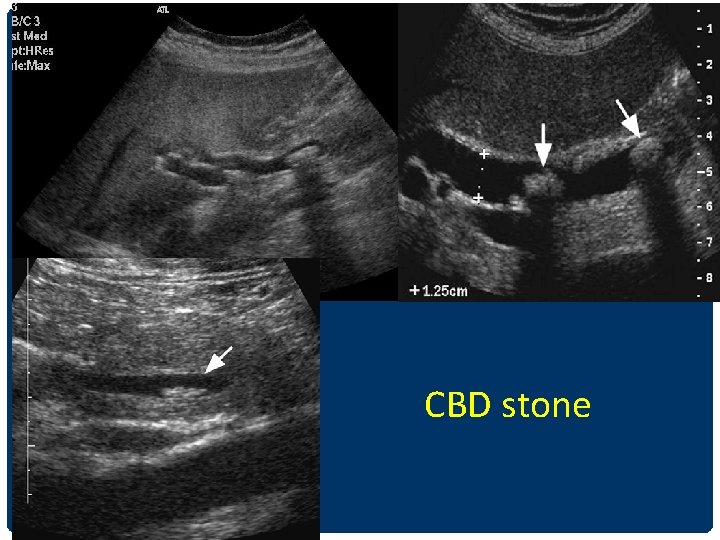

CHOLEDOCHOLITHIASIS/STONE • Most common causes of biliary obstruction • Intrahepatic duct stones less common than CBD stones • Gall stone --- 15% ass. with CBD stone • CBD stone ---95% ass. With GS

CBD stone

INTRAHEPATIC DUCT STONES DDx • IHD stones • Intrabiliary gas/ pneumobilia • Hepatic artery calcification